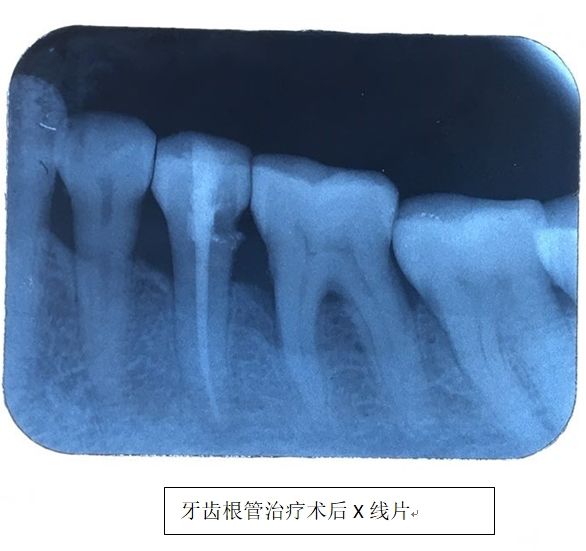

听闻街坊邻居说起,湖南航天医院的口腔科就诊环境有了极大改善,医疗设施越来越完备,医疗技术越来越高,娭毑遂来院就诊。为她进行诊疗的是邓旋医师,在详细询问病史和缜密地检查后,邓旋判断娭毑的症状是由牙齿引起,初步诊断为牙髓炎,排除张娭毑自己怀疑的神经疾患。找出病因后,邓旋医师便开始着手对张娭毑的患牙进行治疗。

过了几天,张娭毑欣喜不已地来院复诊。原来患牙经过根管治疗后,左面部神经疼痛症状明显消退,眼泪也不异常流出了,脸上露出了微笑,心情也开朗了许多,生活质量也有了极大提高。医生随诊时还听说最近她还和家人出去旅游了……

另外还可以进行口腔科根尖片的拍摄,还能进行全景片、头颅侧位片、颞下颌关节片、上颌窦片、牙齿CT等检查,能辅助诊断及治疗工作的顺利进行。